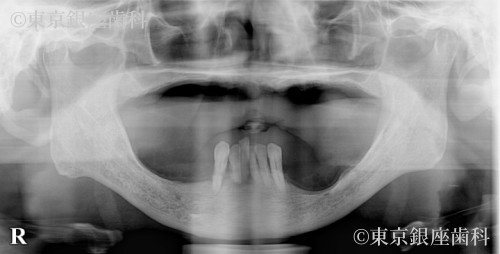

Before

疾患 歯牙部分欠損

施術内容 ワンデイインプラント

嘔吐反射で入れ歯が使えず複数医院で治療を断られていたが、当院の精密診断でワンデイインプラントが可能と判明。現在は上下とも安定。

上下ワンデイインプラント(サイナスリフト併用)